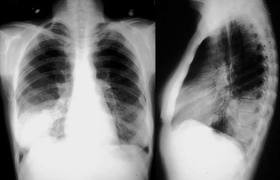

Пневмония

Диагностика пневмонии позволяет решить несколько задач: выявить тяжесть, этиологию, взаимодействие с другими процессами. Само заболевание характеризуется интоксикацией, развитием лихорадочных процессов, кашлем. При этом при рентгенографии выявляются такие изменения: интерстициальные (определения легочного рисунка), паренхиматозные (диффузны, очаговые затемнения).

Также проводятся бакпосевы, анализы крови. Необходимо сразу выявить возбудителя, что даст правильную картину течения, поможет назначить лечение.

При лечении требуется госпитализация, соблюдение постельного режима, высококалорийное питание, очень обильное питье. Основное лечение – антибактериальная терапия, антибиотики подбираются только лечащим врачом, возможно до выявления возбудителя. Обычно используют пенициллины, фторхинолоны, цефалоспорины, аминогликозиды, карбапенемы. Также применяют иммуностимуляторы, отхаркивающее, жаропонижающие, антигистаминные препараты. Читать далее